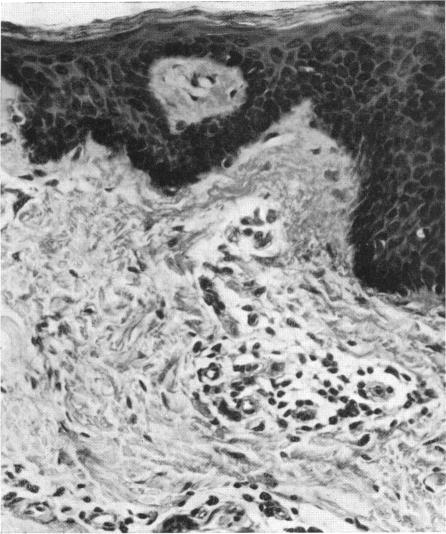

In this review, the author discusses separately the cutaneous and the ocular aspects of the symptomatology, pathology and pathogenesis of onchocercal infections. Original results are also reported on dermal onchocerciasis.The less well known lesions are described in greater detail than the better-known. Among the former are the association of cutaneous tumours with dermal onchocerciasis, depigmentation of the skin, and the posterior ocular lesions. In dealing with the pathology of dermal onchocerciasis, the author demonstrates that the main effect of the death of the parasites is on the blood vessels, causing them to become atrophic so that the consequent anoxia gives rise to the better-known, more obvious changes of pachyderma.The relationship of allergic and nutritional factors with the different lesions is discussed. It is pointed out that the evidence connecting the symptomatology with allergy is not very conclusive while the evidence connecting nutritional factors with the ocular manifestations continues to mount.